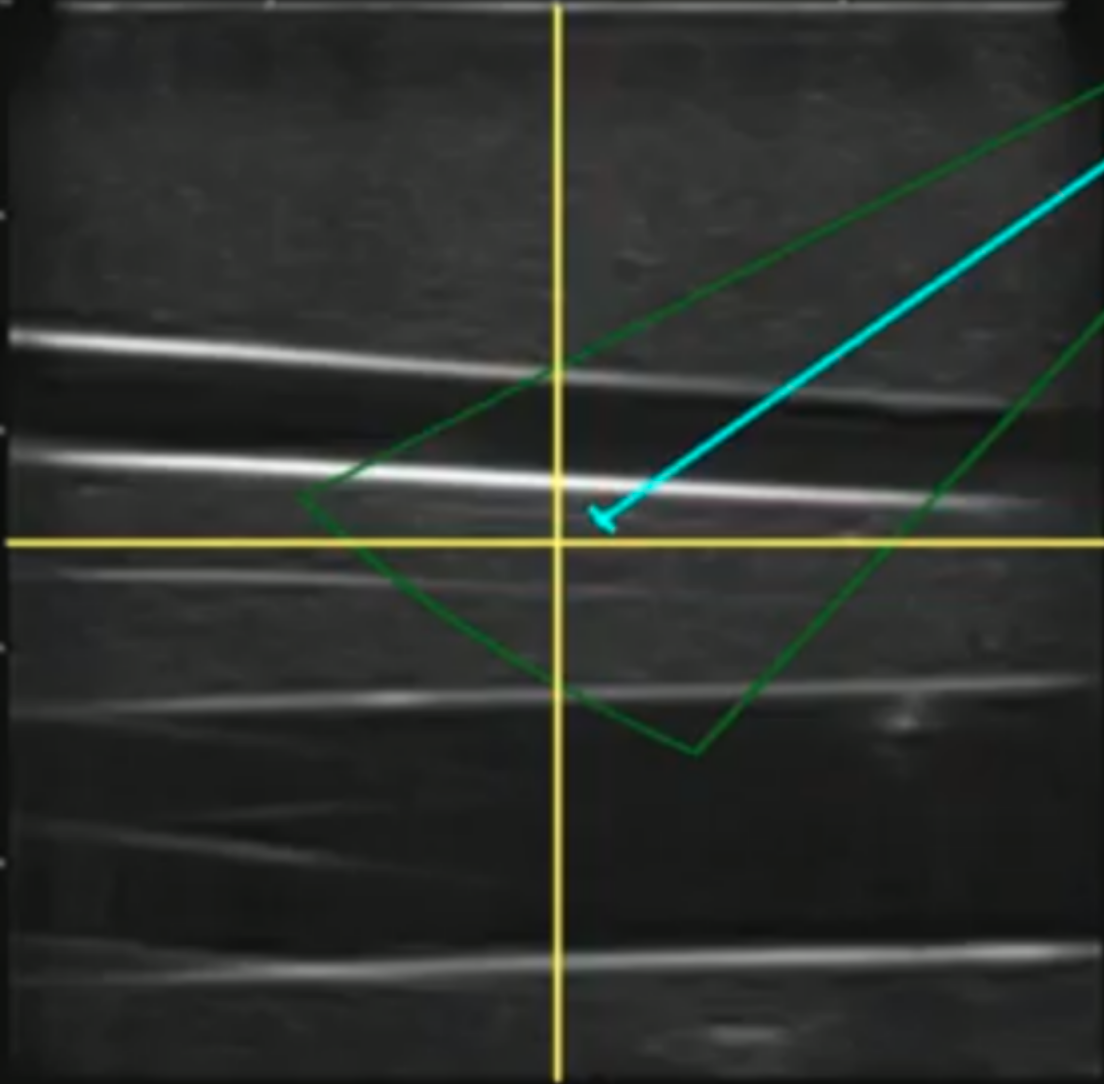

IV-B Image-space controller (4)

Bridging the gap between the automated ultrasound scanning and needle insertion, an image-space controller was developed to augment the user’s perception and control of the robot arm in conjunction with the ultrasound images. This system allowed for a single user to navigate the subdermal environment in order to view different, previously unobservable features. Previously we relied heavily on the UR3e pendant in conjunction with the monitor attached to the ultrasound, which overall lead to a divided operator attention and unintuitive control of the UR3e which required the user to command movement’s in the robot’s base frame. This process was necessary to align the ultrasound probe parallel to the femoral artery or vein as well as the surface of the skin as required for good ultrasound imaging and guide wire insertion as described by the Seldinger technique.

Our approach relied heavily on an augmented ultrasound image (Fig. 4). After a simple calibration which allowed us to convert ultrasound image space into real-world distance, a click on the image frame commanded the robot to move the ultrasound probe so that point was now located in the center of the frame. We also added additional buttons to control the rotation and non-planar position of the robot. This intuitive motion model made it possible for a user to simultaneously center the vessel in the center of the image and rotate until the vessel is transverse to the ultrasound probe (4).

IV-C Needle Insertion (5-7)

The needle control algorithm is designed to take a user-selected point in the ultrasound image and drive the tip of the needle to that target. To aid the user in this task, we used the GUI to add an overlay of the work space of the needle, spanning the limits of the linear and angular degrees of freedom (Fig. 4). By clicking on the image within this workspace, the user could quickly and intuitively drive the needle anywhere within the work area. The calibration to calculate the transformation between actuator positions and ultrasound image space was done in a water bath.

In practice we found that this calibration was accurate enough for user control. There is a wealth of literature dedicated to the tracking of needle bending using ultrasound images [18, 29, 8]. Although due to complex needle-tissue interactions this kind of complex needle tracking will be necessary for full automation of needle insertion, it was accurate enough for the operator to use as a visual aid when planning a needle insertion, Fig. 4.

To correct errors in the kinematic estimate of the needle tip the users also relied on a so called ”needle tweak controller.” By clicking along the axis of the needle the user could adjust the needle depth in the ultrasound frame by visually estimating the error in the kinematics.